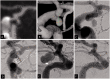

Results: From July 2009 to June 2019, 338 aneurysms (190 unruptured aneurysms and 148 ruptured cerebral aneurysms) underwent coiling and satisfied our study criteria. Among these patients, 23 patients (19 ruptured and 4 unruptured aneurysms) were found to have recurrent aneurysm. Of those, 4 were found to have early major aneurysm regrowth occurring within 6 months after coiling (1.2%). The detection of the EMR was as early as 4 weeks and as late as 20 weeks after the initial coil embolization. The average detection time was 10 ± 7.2 weeks (mean ± SD, range:4-20 weeks). In each case, the recurrent aneurysm cavity was more than twice the initial size of presentation. All aneurysms with major recurrence were ruptured with low aspect ratios (dome height to neck ratio) and involved a communicating segment. All patients underwent successful retreatment of the recurrent aneurysm with good outcome.

Conclusions: Early major recurrence of treated aneurysms is a rare but important complication that harbors an impending risk of re-rupture. Early control angiography after endovascular coiling may be warranted for small ruptured aneurysms, even in cases in which the initial result seems technically satisfactory.